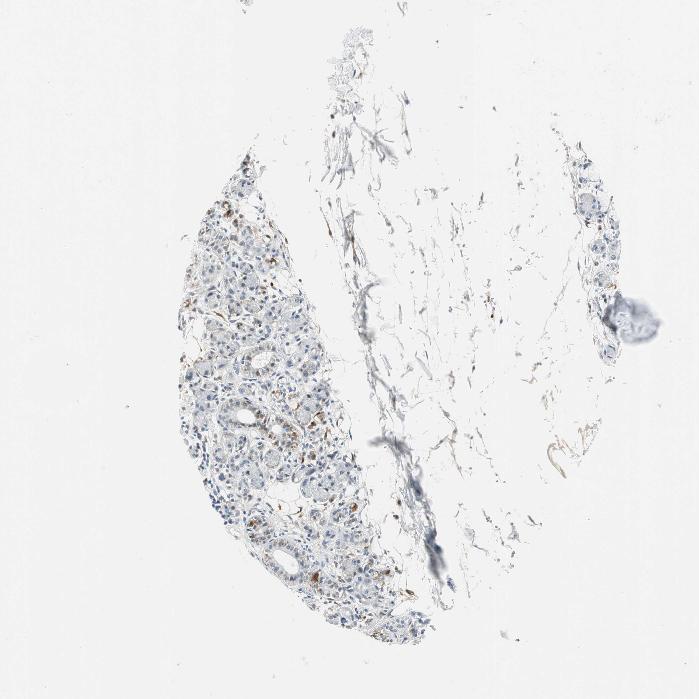

SOFT TISSUE 2 - Antibody stainingi

Antibody staining in the annotated cell types in the current human tissue is reported as not detected, low, medium, or high, based on conventional immunohistochemistry profiling in selected tissues. This score is based on the combination of the staining intensity and fraction of stained cells.

Each image is clickable and will lead to virtual microscopy that enables deeper exploration of all samples and also displays staining intensity scores, fraction scores and subcellular localization as well as patient and tissue information for each sample.

Antibody HPA006493

Fibroblasts Low

Peripheral nerve Not detected